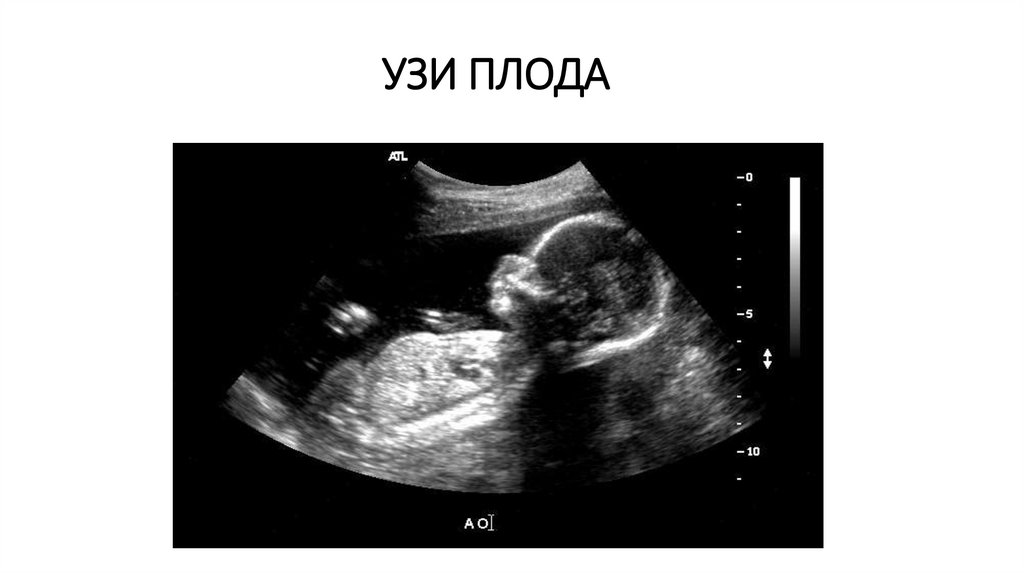

УЗИ ПЛОДА

Плод и плацента: определение срока беременности, многих аномалий развития плода, его функционального состояния